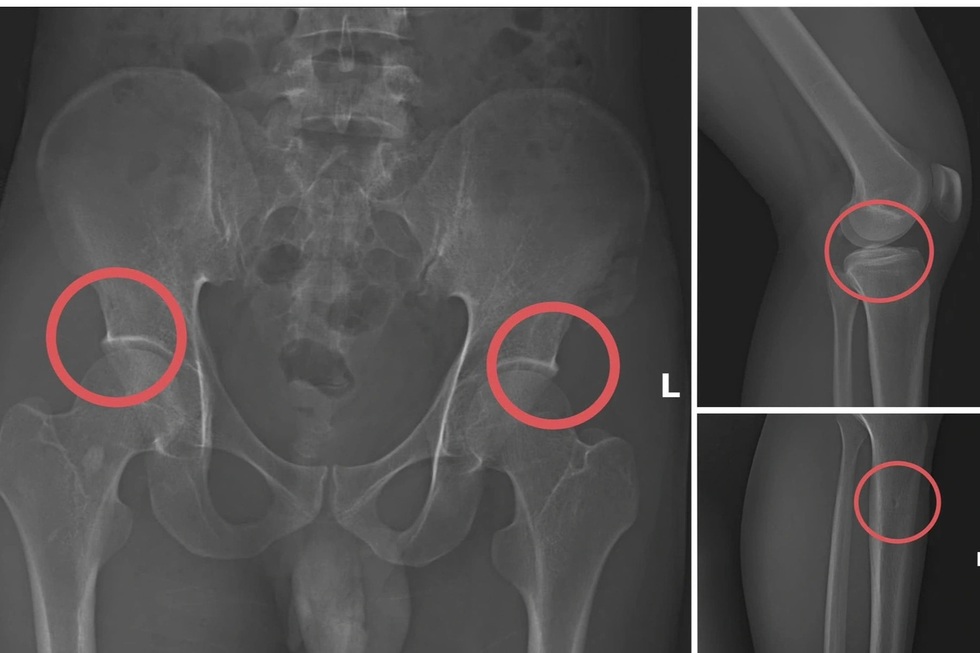

Một số tổn thương xương do các đối tượng tạo ra nhằm trục lợi bảo hiểm nhân thọ (Ảnh phim chụp XQ, Công an tỉnh Phú Thọ cung cấp).